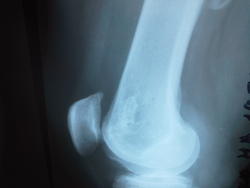

Немного подредактировал изображения:

bedro.jpgbedro2.jpg

Спасибо огромное, так более четко,особенно в боковой проекции.Никаких нвых предположений?Похоже на остеоид-остеому,но плотная часть какая-то неоднородная,склеротический ободок присутствует.А может это киста старая?

Может быть, много чего... Кисты версия заинтриговала. Я такого себе бы сейчас не позволил уже.) Насчёт остеоид-остеомы - вместо склеротического ободка здесь ободок локального пороза - то есть нет в гнезде типичного яйца.)

Согласна,классического плотного центра нет,  но образование имеет достаточно четкие контуры ,периферические отделы намного плотнее, чем центральная часть, как скорлупка, а за ней уже идет зона разряжения костной структуры.Короче говоря, вызвана на дообследование, будем переснимать на цифру...

В м\т на боковой проекции позади бедренной кости тень имеется.

Тень такую мышечный компонент даёт. Это нормально - гомогенная и плотность обычная.